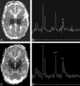

Leukoencephalopathy - thalamus and brainstem anomalies - high lactate

Brainstem anomaly

High lactate

Thalamus anomaly